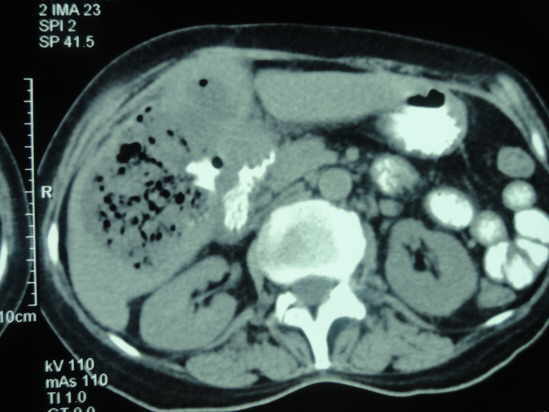

Tomografía Axial Computarizada de Absceso Hepático Amebiano

TAC abdominal con contraste es la técnica de elección para el diagnóstico de los abscesos hepáticos

La sintomatología del absceso hepático amibiano se ha englobado en lo que se denomina la “triada clásica”: hepatomegalia, dolor en hipocondrio derecho y fiebre, asociados a leucocitosis en presencia de neutrofilia y pruebas serológicas para E. histolytica positivas.